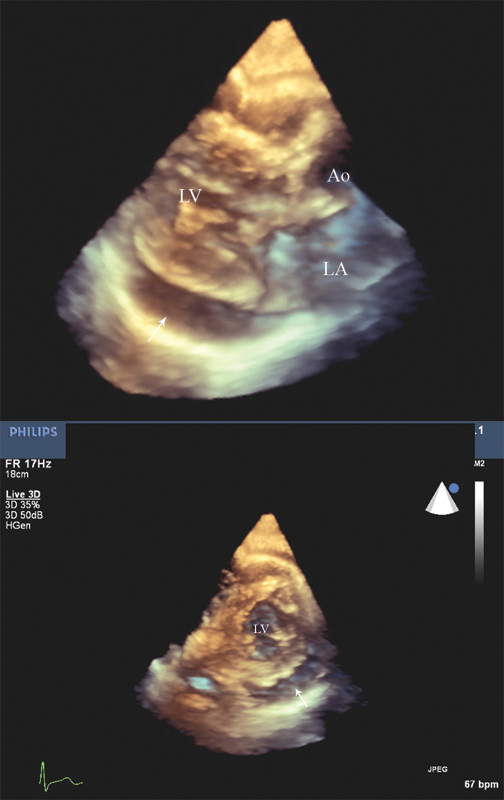

فحوصات تشخيصية لبعض امراض القلب والشرايين التاجية